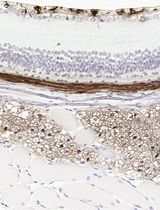

采用 Davidson 固定液和黑色素漂白法优化小鼠眼组织切片的免疫组化染色

Anne Nathalie Longakit [...] Catherine D. Van Raamsdonk

2025年11月20日 1628 阅读